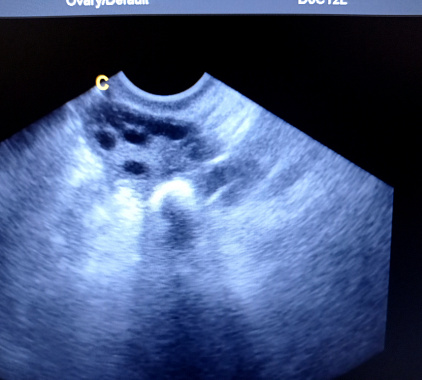

- поликистоз: определяется много мелких фолликулов по периферии, увеличивается объем, изменяется строма и гормональный фон;

Фотогалерея

Фолликулы – это «пузырьки», где созревают яйцеклетки. В нормальном состоянии их количество и диаметр меняются в течение менструального цикла: появляется доминантный фолликул, затем формируется желтое тело. Если фолликулов слишком много и они мелкие, это может свидетельствовать о поликистозе или гормональных нарушениях. Интерпретировать картину должен гинеколог по дню цикла и вашим симптомам.